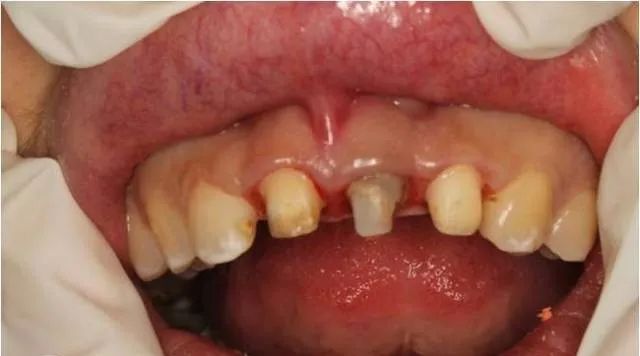

基牙备置

临时冠修复

术后两周拆线后口内情况

三个月后修复牙体制备后